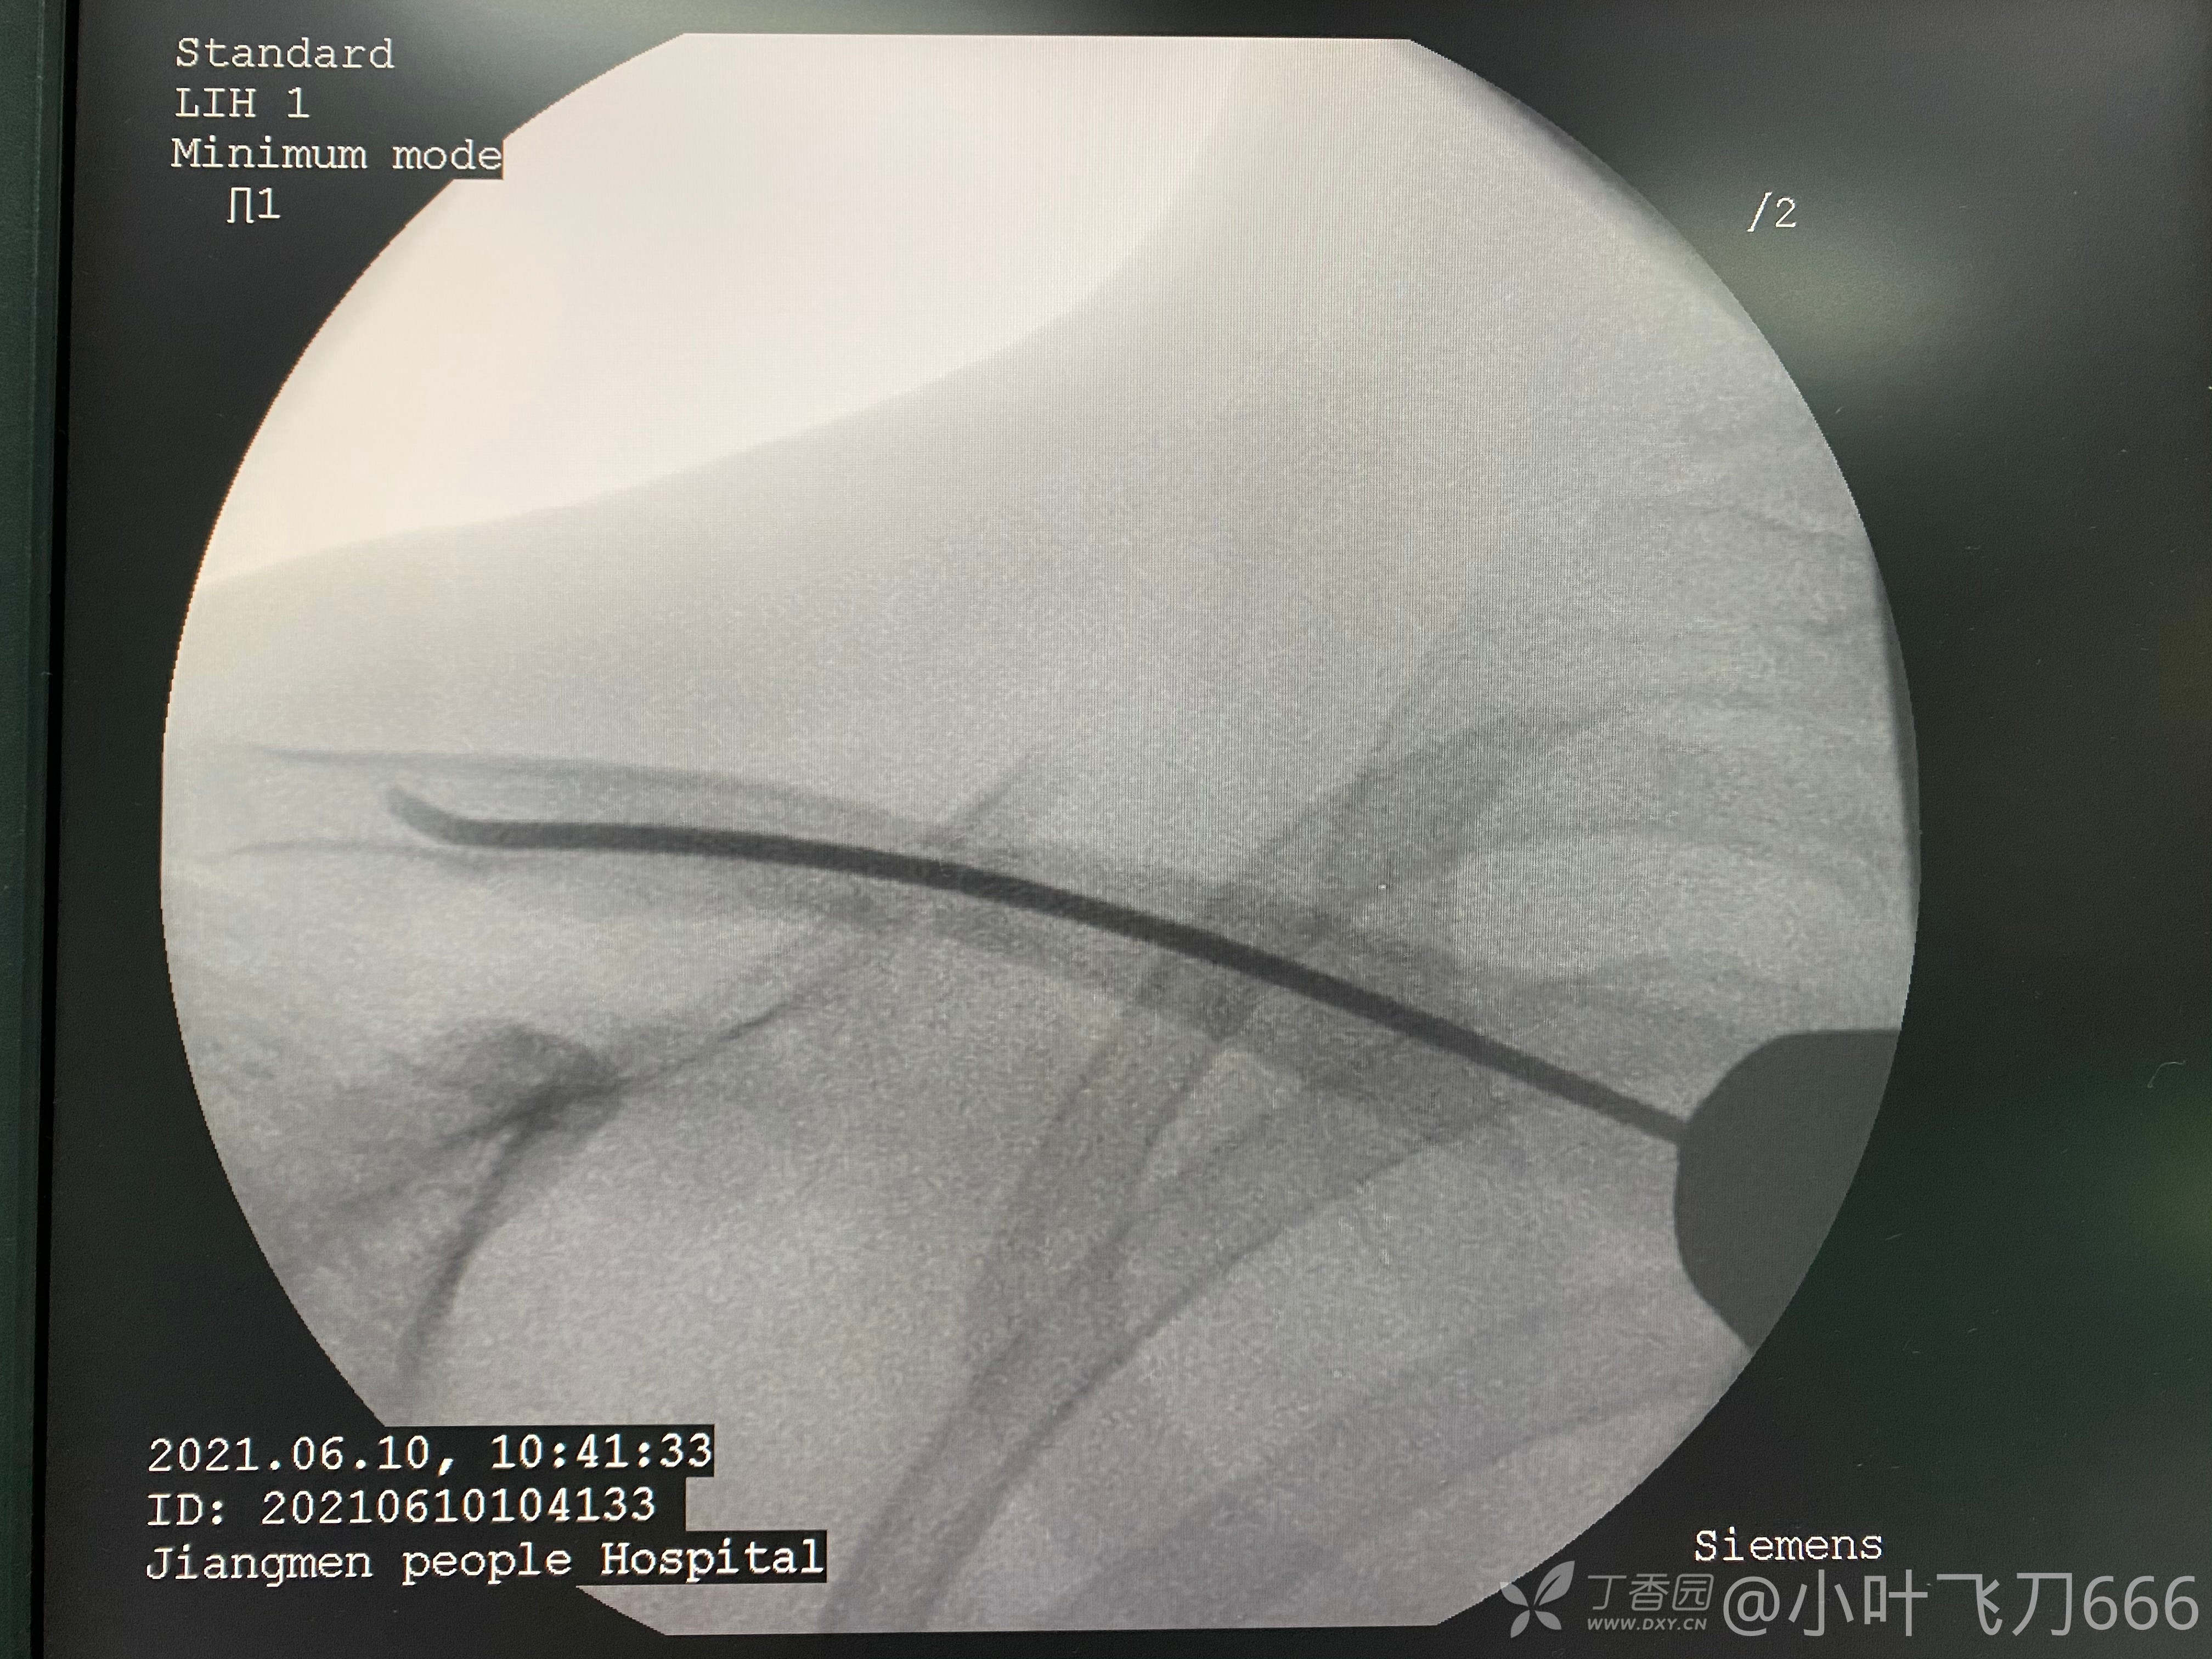

手术方案闭合复位弹性髓内针内固定,髓内针入针困难的话可以小切口切开同直径克氏针远近端扩髓,不过一般不需要。手术重点无非是2把点式复位钳技术,或者点式复位钳结合操纵杆技术,进针点锁骨近端干骺端1-2cm。

其次是髓内针选择,髓腔直径1/2—1/3根据情况选择。儿童骨折术后需要悬吊4周,毕竟儿童骨折手术弹性内固定需要外固定支持。